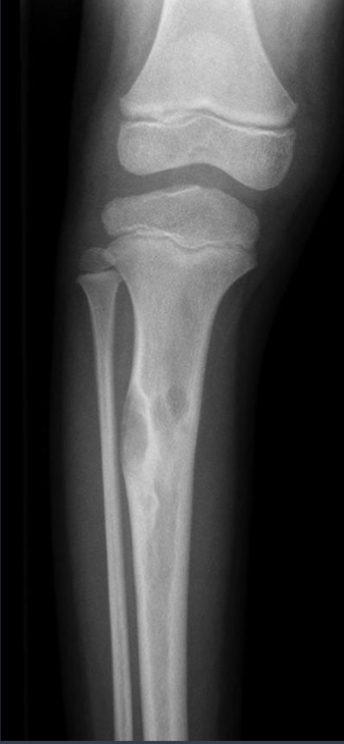

what is this?

aneurysmal bone cyst (ABC)

highly expansile

lytic, septated

eccentric

markedly thinned cortex

metaphyseal, can extend to epiphysis ITS THE ONLY BENIGN TUMOR TO CROSS GROWTH PLATE

periosteal response common